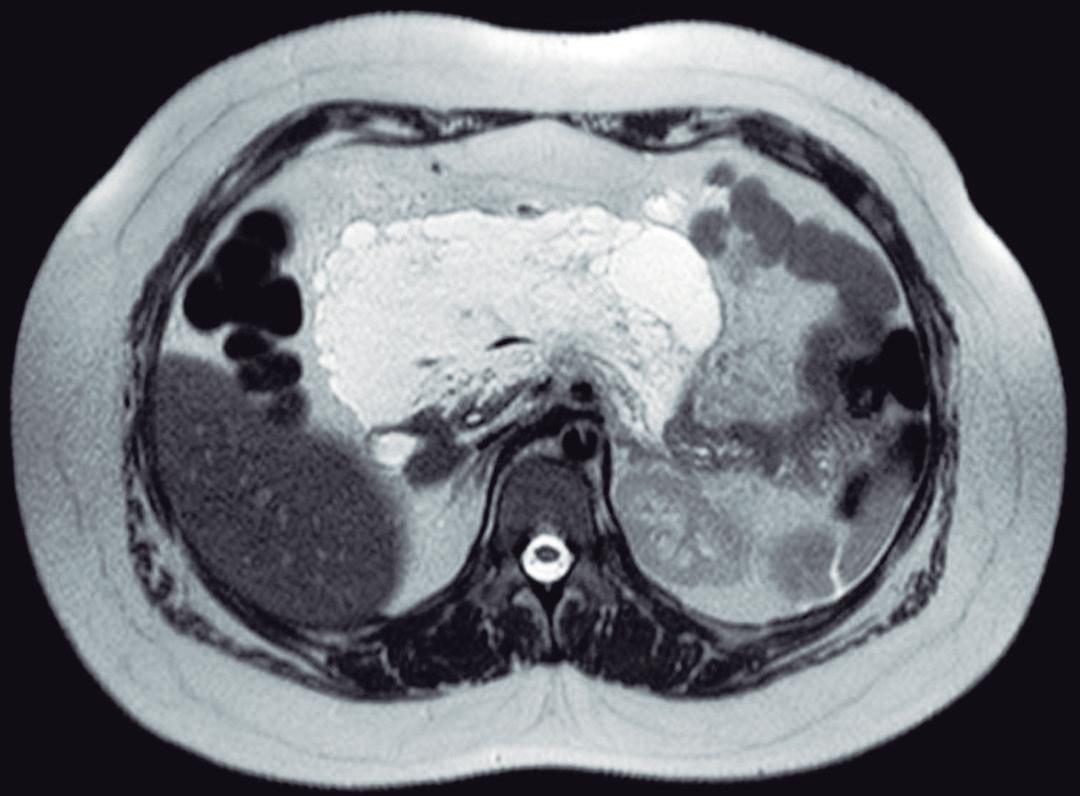

Evaluación endoscópica e histológica

La endoscopía superior es un procedimiento fundamental para el diagnóstico, la evaluación de la respuesta al tratamiento y el monitoreo a largo plazo de la actividad de la EEo. Los hallazgos endoscópicos típicos incluyen edema (reducción de vascularidad), anillos esofágicos fijos, exudados blancos, surcos longitudinales, estenosis, estrechamiento de la luz esofágica, friabilidad de la mucosa (mucosa en papel crepé) y una consistencia firme de la mucosa al realizar biopsias (signo de “tracción" o "resistencia”) en pacientes con fibrosis (Figura 1). Estos hallazgos no son patognomónicos y no constituyen un criterio diagnóstico; sin embargo, cuando se evalúa de forma cuidadosa, en la gran mayoría de los casos se pueden observar.19-21

En el panel A se observa un esófago con edema difuso y pliegues longitudinales; en el panel B se aprecia edema con pliegues y exudados blanquecinos; en el panel C se evidencia un estrechamiento luminal acompañado de anillos esofágicos y exudados; y en el panel D se muestra un desgarro mucoso posterior a la dilatación con bujía de Savary, hallazgo esperado tras este procedimiento terapéutico.

Figura 1. Características endoscópicas de la esofagitis eosinofílica